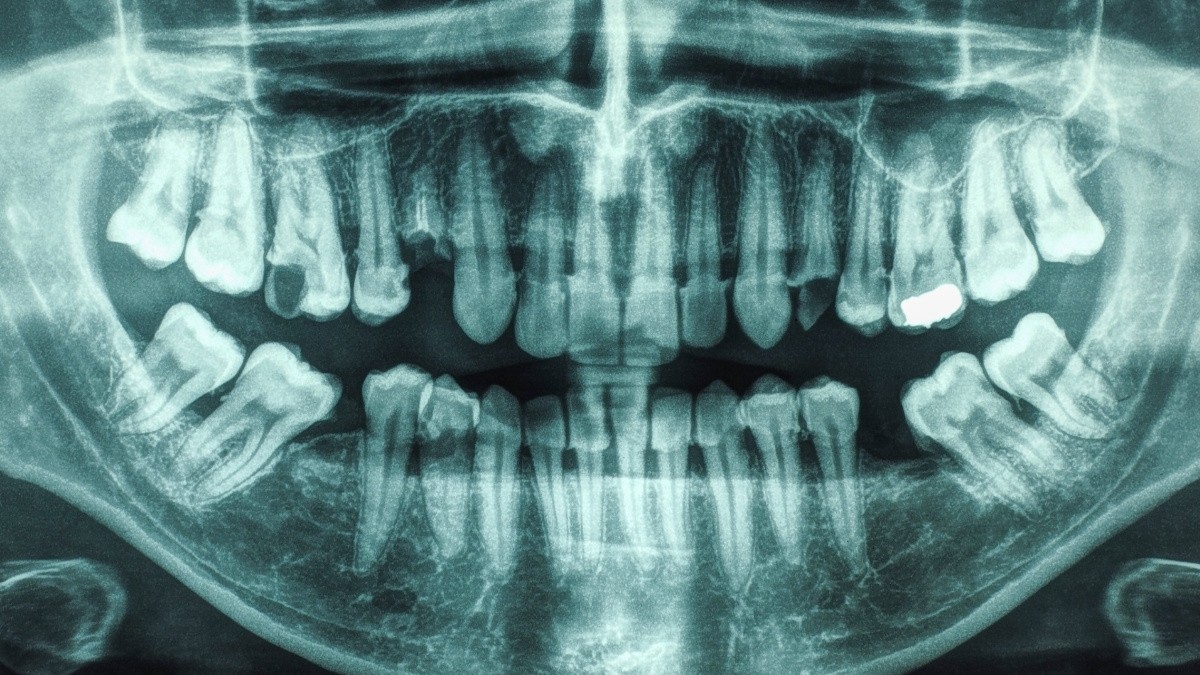

Un nuovo studio durato 21 anni ha rivelato un legame significativo tra scarsa salute orale – in particolare, la combinazione di malattie gengivali e carie – e un rischio notevolmente più elevato di ictus. Sebbene ciascuna condizione sia stata precedentemente associata individualmente all’ictus, questa ricerca evidenzia il rischio amplificato quando si verificano insieme.

I ricercatori dell’Università della Carolina del Sud hanno monitorato la salute di 5.986 adulti (con un’età media di 63 anni) per oltre due decenni, concentrandosi su individui senza una storia precedente di ictus o malattie cardiache. Hanno classificato i partecipanti in base alla loro salute orale: buona salute orale, solo malattie gengivali o entrambe le malattie gengivali e carie.

Gli autori dello studio sottolineano che i risultati dimostrano un’associazione, non una relazione causale diretta. Tuttavia, ipotizzano che il collegamento probabilmente derivi dalla diffusione dell’infiammazione e dei batteri dalla bocca ad altre aree del corpo.

Questa teoria è in linea con ricerche precedenti che hanno identificato i batteri orali nelle placche arteriose, i depositi di grasso che possono restringere le arterie e limitare il flusso sanguigno. La presenza di batteri in queste placche può potenzialmente innescare la formazione di coaguli e portare a ictus ischemici (ictus causati da coaguli di sangue).

I risultati dello studio suggeriscono che il miglioramento della salute orale potrebbe essere una componente importante delle strategie di prevenzione dell’ictus. I ricercatori hanno anche confermato i vantaggi di controlli dentistici regolari: le persone che hanno riferito di visitare regolarmente il dentista avevano significativamente meno probabilità di avere sia malattie gengivali che carie insieme e riducevano il rischio di malattie gengivali.